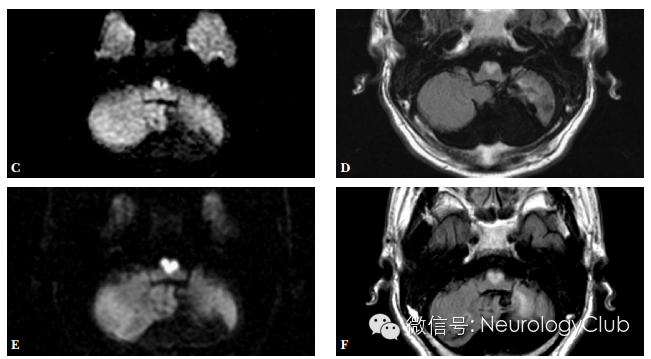

延髓内侧由椎动脉和脊髓前动脉分支供血,其中延髓内侧上1/3由椎动脉旁分支供应,下2/3由双侧脊髓前动脉及其汇合而成的前正中动脉延髓支供应。双侧延髓内侧梗死血管病理学改变以大动脉粥样硬化最为常见,其次是小穿支动脉病变,另外也有栓塞、动脉夹层、动脉炎或合并先天血管变异等病因报道。影像学特点头颅MRI检查,尤其是DWI对双侧延髓内侧梗死的早期诊断有很大的帮助。其影像学表现为磁共振显示双侧延髓内侧类似“心型”或“Y形”的长T1长T2信号影,DWI高信号,ADC低信号,符合梗死改变,具有特征性的诊断意义。

引自:A case of bilateral medial medullary infarction presenting with "heart appearance" sign.Tokai J Exp Clin Med. 2007 Sep 20;32(3):99-102.

引自:The "heart appearance" sign in MRI in bilateral medial medullary infarction.Postgrad Med J. 2011 Feb;87(1024):156-7.